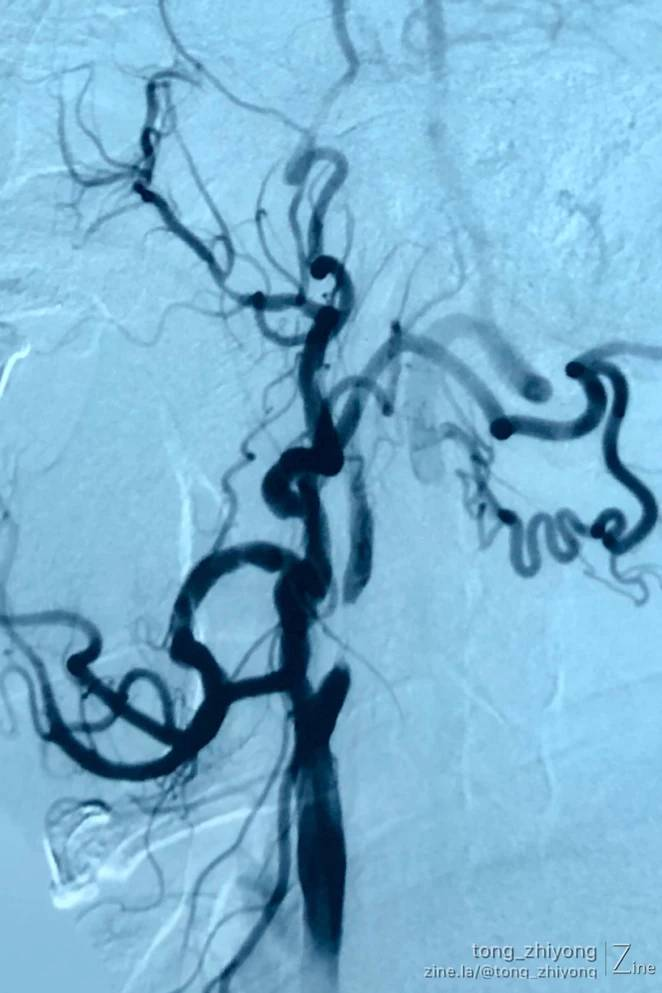

下面这个颈动脉重度狭窄的典型病例,老年,男性,经历了两次手术,体现了两种外科技术的合作、补救:

左侧颈动脉支架植入术;

十一个月后,斑块内出血,局部血栓形成,症状性极重度再狭窄;

左侧颈动脉内膜切除,取出支架,补片成形术。

症状性左侧颈动脉重度狭窄

雅培,锥形支架,6-8*40mm

支架植入术后颈动脉狭窄解除

血管造影显示:颈动脉极重度再狭窄,不能确认支架和远心端颈内动脉之间直径的差异。